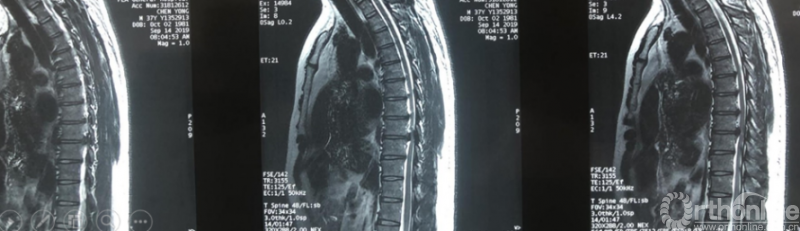

术前诊断及评分

JOA评分:5分

ASIA等级:C级

诊断:

1:胸椎间盘突出伴钙化下肢不全瘫

术前资料